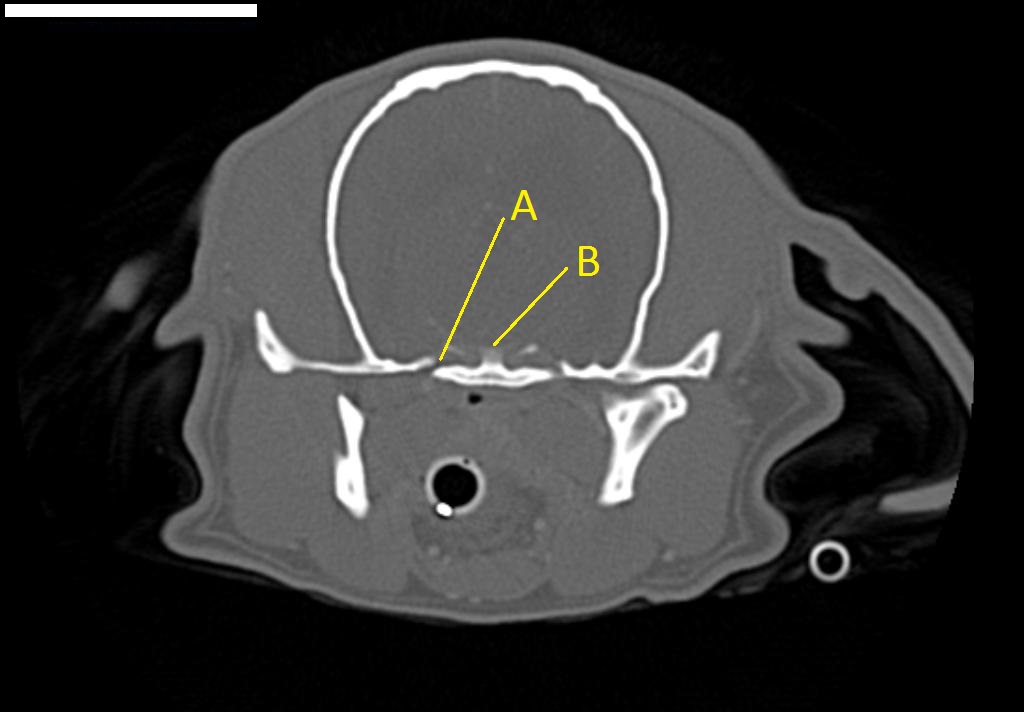

Q. Identify the structures labeled below:

A. foramen ovale

B. dorsum sellae